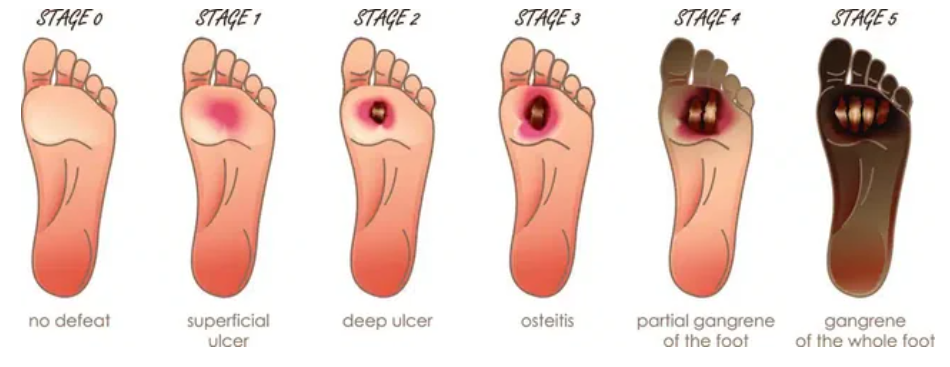

Most don’t feel it happening until it begins affecting their eyes, nerves, feet and even their heart increasing Diabetes Neuropathy symtoms.

• Feel numbness or tingling in hands and feet

The hidden symptoms of diabetes may be more dangerous than you think. Prevention starts with awareness.